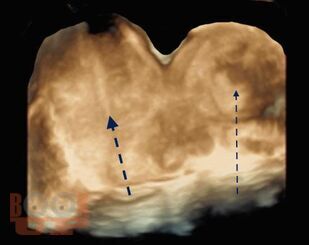

Интерстициальная и угловая (ангулярная) беременность

В учебно-методическом пособии приведен сравнительный анализ существующих методов лечения беременности в интерстициальном отделе маточной трубы и ангулярной беременности. Подробно изложен собственный запатентованный протокол лечения интерстициальной трубной беременности в зависимости от данных ультразвукового исследования в совокупности с уровнем ХГЧ в сыворотке крови беременной, разработанный авторами. Данный протокол позволяет на основании полученных диагностических данных выбрать оптимальный метод органосохраняющего лечения, определить методы последующего контроля состояния пациента.